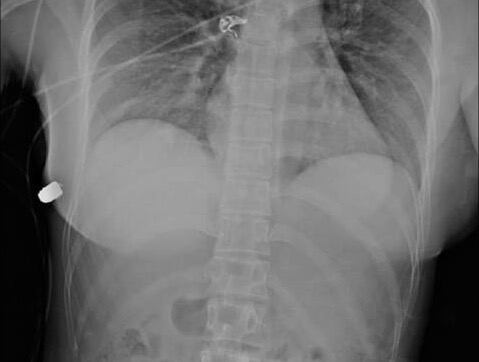

Usando radiografías de trauma, los médicos detectaron la bala en la pared torácica lateral derecha, además de una costilla fracturada y burbujas de aire en el seno izquierdo, concluyendo que este viajó desde el seno izquierdo hasta la pared torácica derecha. Por lo demás, la mujer resultó notablemente ilesa.